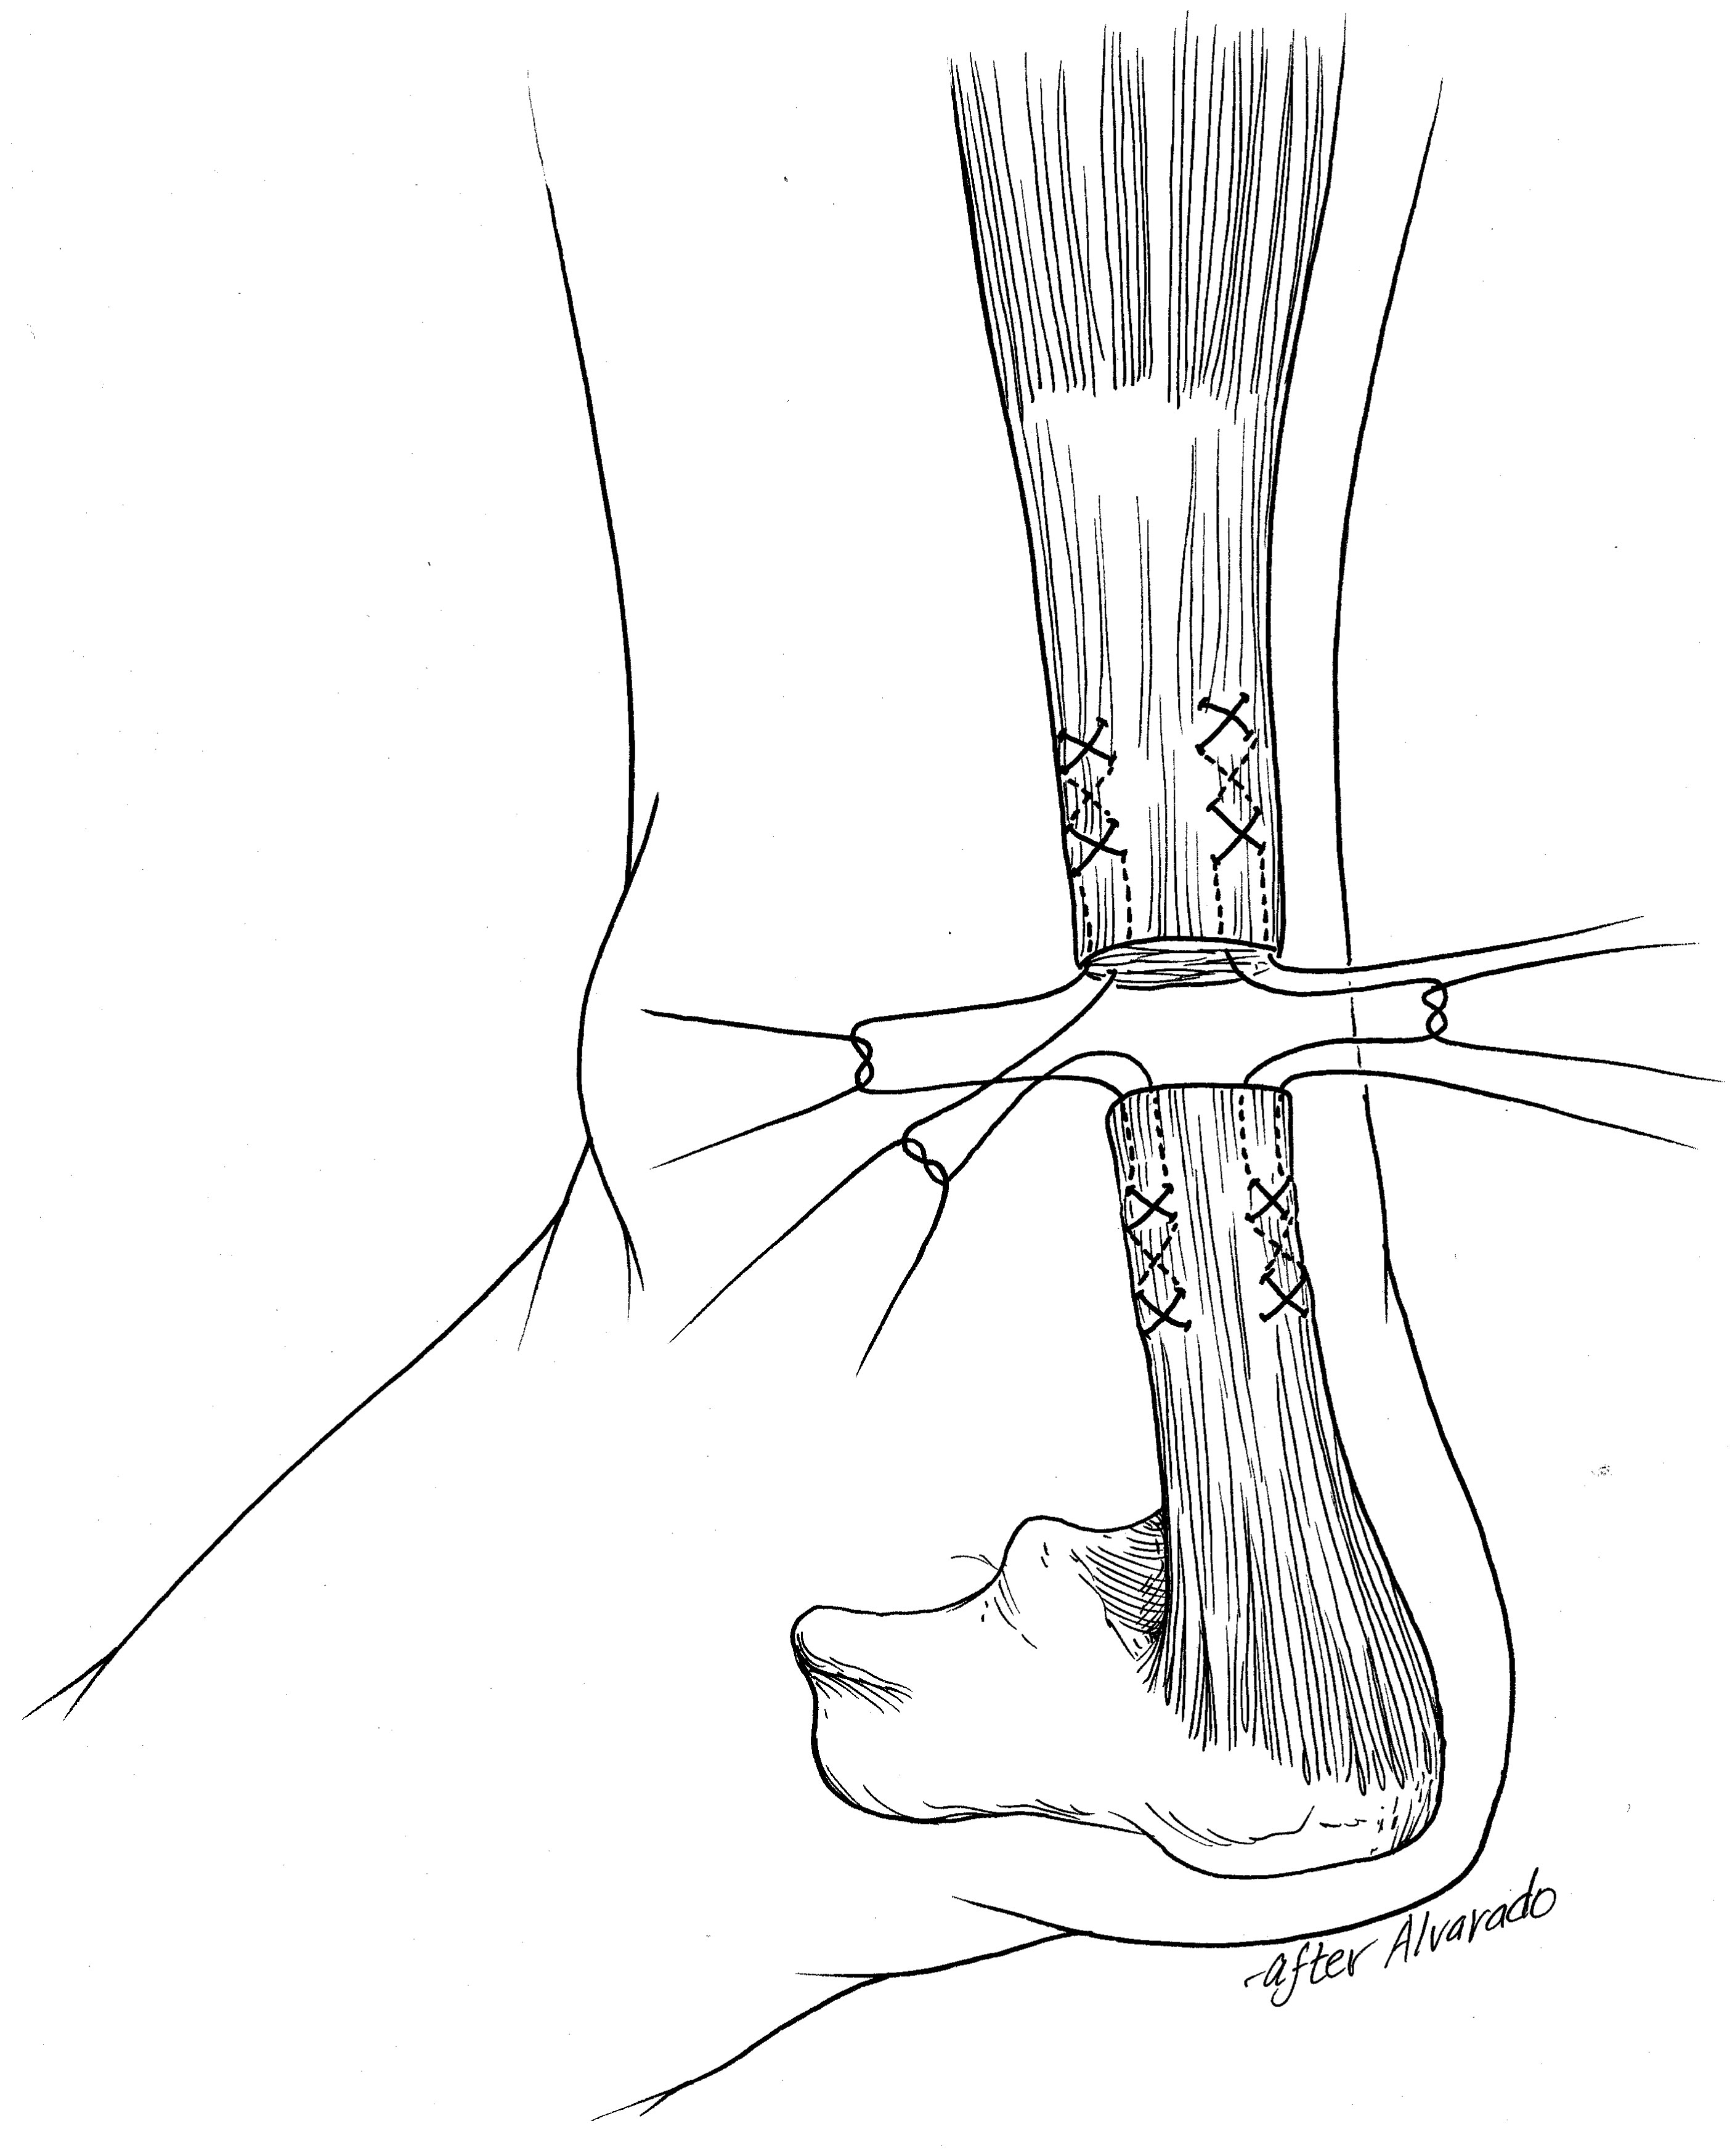

• Tears of the middle part of the tendon are repaired using sutures to bring the torn edges together. There are several techniques which can be used to perform this repair. Your surgeon can discuss these options with you. Newer techniques involve smaller skin incisions, and these are referred to as "minimally invasive surgery (MIS)."

To repair a tear of the middle part of the Achilles tendon, the surgeon will perform one of a number of different techniques. The technique shown here involves sutures at the top and bottom part of the tendon, which is then tied in the middle to bring the torn tendon edges together. Other techniques are available, and your surgeon can discuss these with you.

Reproduced from Saltzman CL, Tearse DS: Achilles Tendon Injuries. J Am Acad Orthop Surg 1998;6(5):316-325.